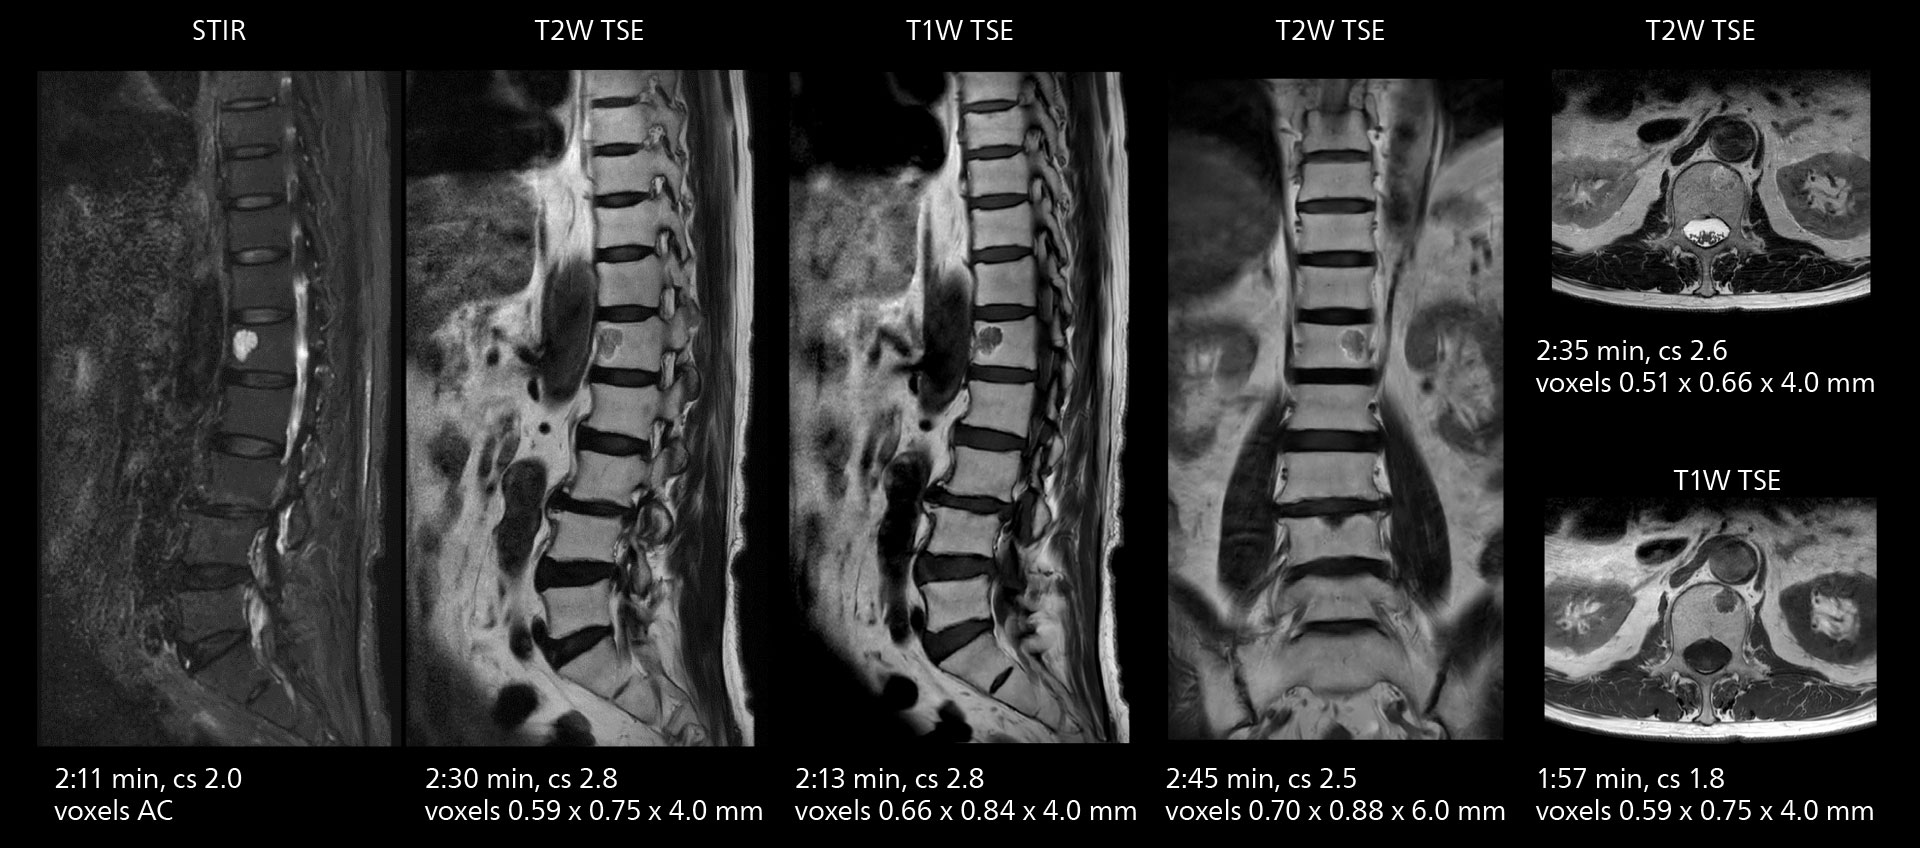

Lumbar spine MRI

Crisp images are obtained with high resolution and short scan times using Elition X. A cyst can be seen.

The high performance of the Vega HP gradients is particularly impressive in DWI. “The Vega HP gradients enable us to scan faster and use b-values as high as 2000, for example in prostate DWI and in DWIBS, which provides image quality that is remarkably improved over the previous system and we are able to more easily see lesions.”

The value of the Elition X gradients is also evident in DWIBS studies. “The fact that we can consistently obtain distortion‐free DWIBS while reducing imaging time at three coronal stations is excellent,” Dr. Makuuchi says. “In these patients, it’s also important that the application of Compressed SENSE to T2‐weighted, STIR and mDIXON sequences has no impact on the examination time of whole‐body imaging. As a result of the increased speed and higher image quality we realize, DWIBS studies have now become routine examinations.”